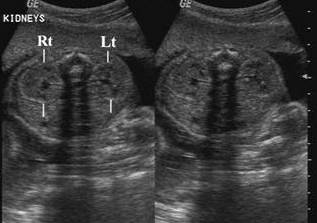

Antenatal hydronephrosis is classified according to severity based on antero-posterior diameter (APD) of fetal renal pelvis in USG. Antenatal hydronephrosis is present if the APD is ≥4 mm in second trimester and ≥7 mm in the third trimester.

- Mild Hydronephrosis (7-10 mm APD) : Monitor with serial ultrasounds every 3 months till resolution. Identify and treat any Urinary Tract Infection(UTI) promptly.

- Moderate to Severe unilateral or bilateral hydronephrosis ( > 10 mm APD) : Refer to a Pediatric Nephrologist. Evaluation and management needs to be individualized.